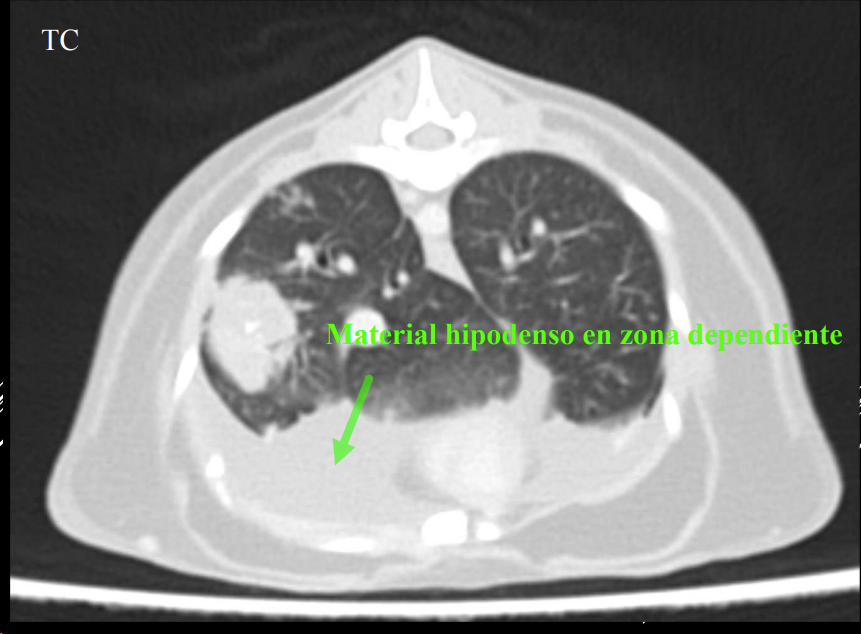

Caudodorsales: hernia paraesofágica, tumores neurogénicos, granulomas.

- Masas mediastínicas (craneodorsales, hilares, caudodorsales, caudoventrales, craneoventrales).

- Linfomas en gato, timomas en perros.